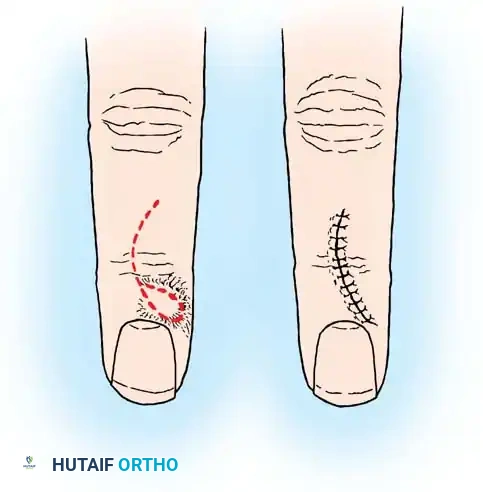

Epidermoid inclusion cysts develop from the traumatic implantation of epithelial cells into the deep subcutaneous tissues or bone. The clinical history almost universally involves a penetrating wound (e.g., a needle prick, thorn, or crush injury) to the palm or fingertip several months or even years prior to presentation.

Clinically, the patient develops a hard, rubbery, non-tender subcutaneous mass. The distal phalanx is the most common osseous site, where the expanding cyst can cause pressure erosion of the bone.

Clinical appearance of an epidermoid inclusion cyst on the index finger following a remote puncture wound.